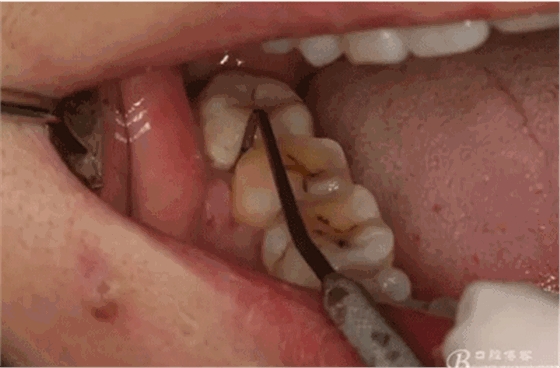

圖4.術(shù)前47遠(yuǎn)中探針檢查,遠(yuǎn)中牙周袋8mm